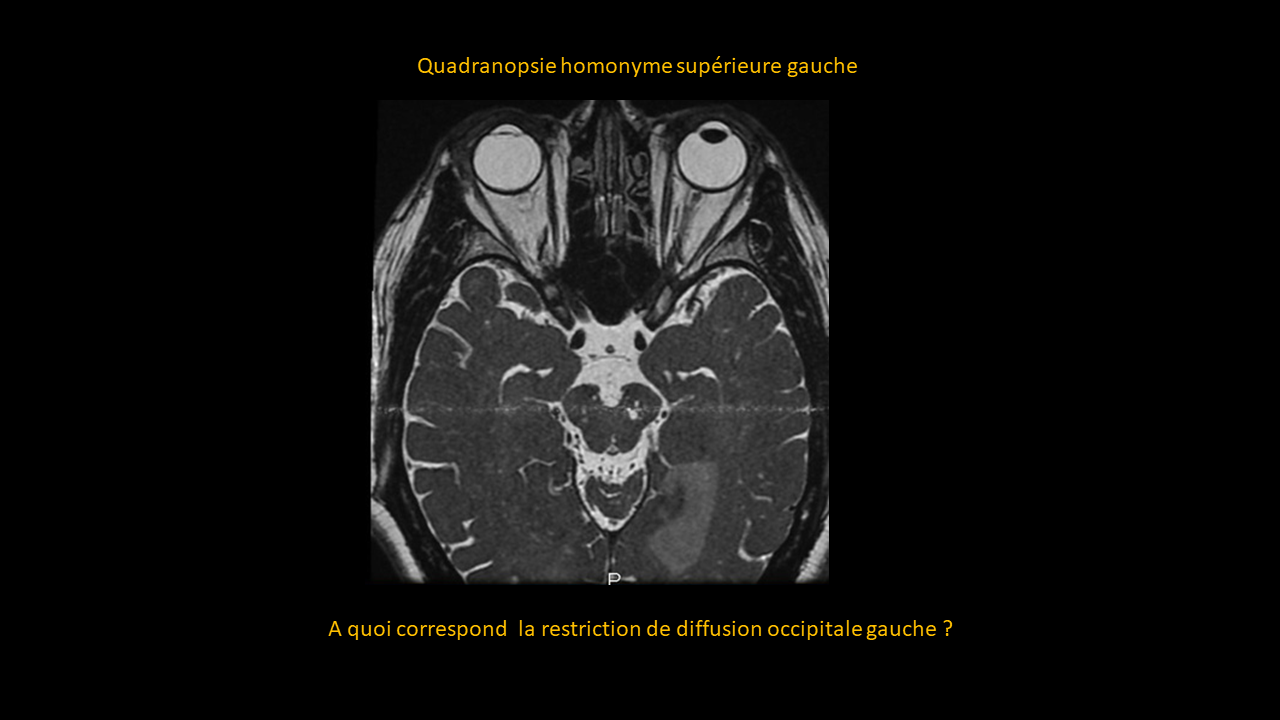

Système nerveux central